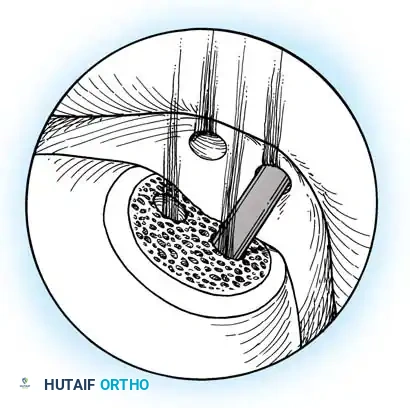

Transmalleolar Portals

As originally described by Guhl, transmalleolar portals are advanced techniques reserved for addressing osteochondral defects of the posterior-central portion of the talus that cannot be reached via standard portals.

- Technique: These portals are established 2 to 3 cm proximal to the tip of the medial or lateral malleolus. Under direct arthroscopic visualization from an anterior portal, a 0.062-inch Kirschner wire is inserted using an anterior cruciate ligament (ACL) tibial guide for pinpoint accuracy. The wire is advanced across the malleolus to drill the chondral lesion. The ankle can be dynamically plantarflexed or dorsiflexed to allow drilling of the lesion in various locations.